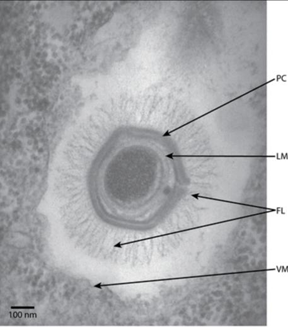

图1. 新冠病毒电镜图

注:黄色:病毒包膜;红色:刺突蛋白(S蛋白);蓝色:核衣壳蛋白及核酸。比例尺 = 100 nm。(图片来源:J, Nitsche A. Sci Rep. 2021; 11(1): 3515)